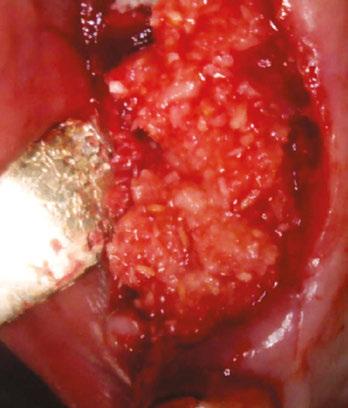

molars in January 2019. The past medical history was significant for cystic fibrosis and depression. He had an allergy to sulfa medications and was taking the following medications: Pulmozyme® (dornase alpha), testosterone, prednisone, and nifedipine. The patient presented with a chief complaint of “I didn’t think I was going to live this long with cystic fibrosis, but I did, and now I am ready to take care of my needs.” The clinical examination was significant for a grossly carious dentition in need of repair (Figure 1). After reviewing several options, it was decided to extract the non-restorable left maxillary first, second, and third molars and to restore the maxillary left first and second molars with fixed implant-retained restorations. With potential healing concerns secondary to his cystic fibrosis, the addition of platelet-rich fibrin (PRF) was discussed. The patient was taken to the surgical operatory where the blood pressure was taken, a pulse oximeter placed, and an IV was started using a 21-gauge butterfly catheter in the right antecubital fossa. PRF protocol was followed using Intraspin® centrifuge (BioHorizons; Birmingham, Alabama), and anesthesia was maintained thereafter using a balance technique. Maxillary left first, second, and third molars were surgically removed, and the resulting extraction sockets were curetted free of granulation tissue. PRF clots and membranes were prepared as described by Choukroun, et al.15 The PRF was mixed 50/50 with MinerOss® mineralized allograft cancellous bone particles (BioHorizons; Birmingham, Alabama) resulting in a “sticky bone preparation” that was placed in the maxillary left first and second molar sockets (Figure 2). Two PRF membranes were placed across the extraction sites (Figure 3), and 3-0 PTFE interrupted sutures were placed affording good wound apposition (Figure 4). Adequate soft tissue healing was observed at a 3-week postoperative check.

Figure 5: Panoramic radiograph taken after healing of the grafted areas prior to implant placement Figure 6: CBCT taken after healing of the grafted areas prior to implant placement Figure 2: Placing the PRF and cortical cancellous bone preparation “sticky bone” into the extraction sockets Figures 3 and 4: 3. Double-layer PRF membrane placed underneath the buccal and palatal flaps prior to closure. 4. 3-0 PTFE suture used to provide closure of the buccal and palatal flaps and stability of the PRF membrane. Notice here primary closure is not necessary. This technique will provide a large band of keratinized tissue for use during implant placement